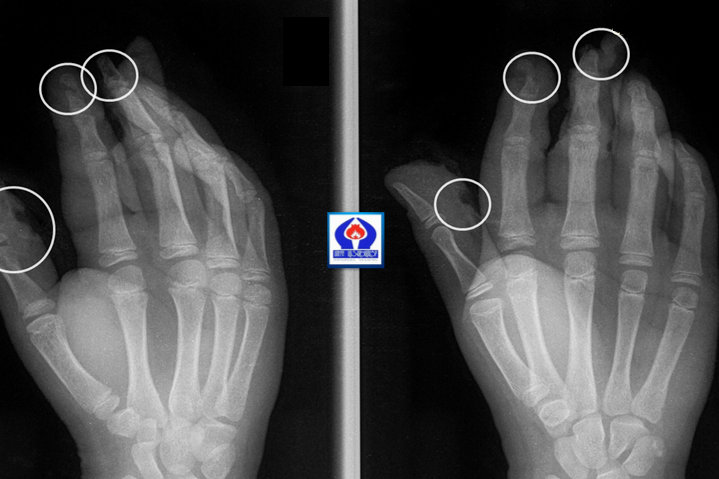

Ամանորի գիշերը «Սուրբ Աստվածամայր» ԲԿ են ընդունվել հրավառության տարբեր տեսակներից տուժած չորս երեխաներ, տարբեր աստիճանի վնասվածքներով:

Երեխաներից երկուսի մոտ եղել են անդամահատված մատներ, ճայթուկը պայթել է հենց ձեռքերի մեջ, մյուս երկուսի մոտ համեմատաբար թեթև վնասվածքներ են եղել:

«Սուրբ Աստվածամայր» ԲԿ-ի պլաստիկ վիրաբույժների կողմից երեխաները վիրահատվել են և դուրս գրվել հիվանդանոցից: